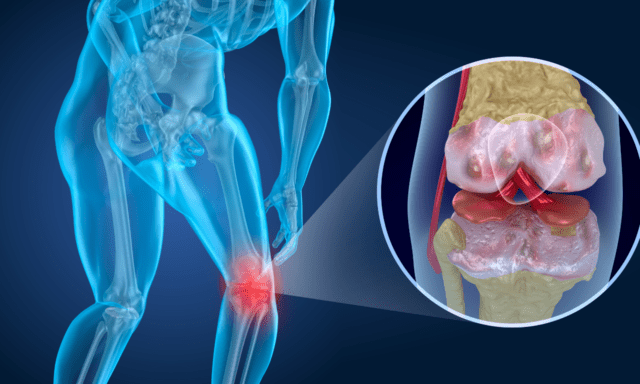

Avsnitt 14: OA i knä

"Knee-d" Jag säger mer?

Den här gången får jag prata med Anthony Teoli om OA i knäet, en utbildare och fysioterapeut som specialiserat sig på OA. Vi diskuterar de tecken och symtom som vi som fysioterapeuter bör titta efter och hur vi kan hjälpa våra patienter. Vi diskuterar fördelarna med träningsterapi och skräddarsyr din strategi för din patient för att säkerställa att de följer och engagerar sig i programmet!